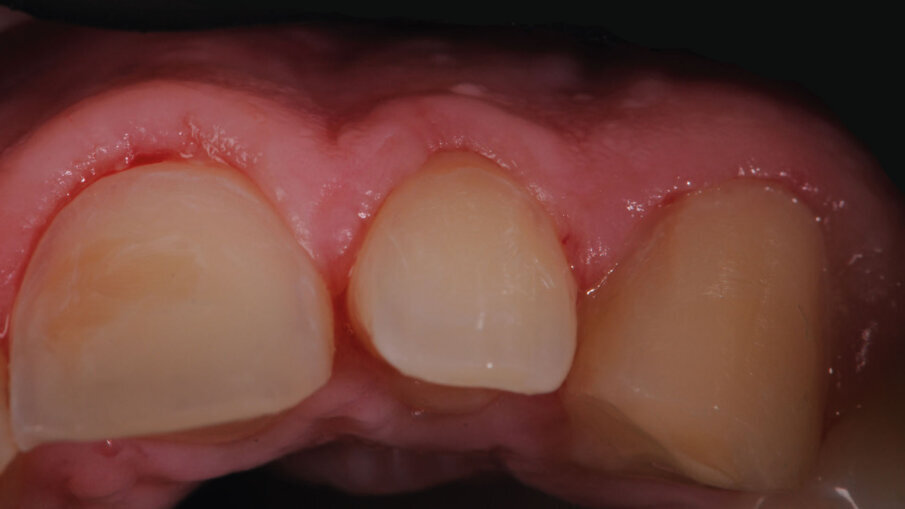

Paziente maschio di anni 26, si presenta alla prima visita con una esplicita richiesta di miglioramento estetico, in quanto non soddisfatto dei suoi denti e di conseguenza del suo sorriso. All’anamnesi riferisce di sorridere poco e con difficoltà, limitando la sua socialità1. Risulta fondamentale in questi casi la fase del colloquio iniziale, per far emergere gli aspetti che il paziente ritiene sgradevoli e cosa invece lo farebbe sentire a suo agio. Si utilizza la fase iconografica dimostrativa con fotografie eseguite su casi simili già finalizzati per mostrare al paziente le fasi cliniche e le possibili soluzioni alle sue richieste. Bisognerà dedicare molto tempo ad ascoltare il paziente, i suoi dubbi e le sue esigenze, capendo da subito le sue aspettative prima di impostare il piano di trattamento. L’esame clinico intraorale, mostra un’arcata superiore con microdonzia a carico degli incisivi laterali 12 e 22, con diastemi e volume ridotto degli elementi canini in proporzione alla dimensione ossea strutturale. Il termine microdonzia2 è spesso abusato, poiché non vi sono dei parametri che la letteratura indica per definire tale situazione, spesso gli elementi microdontici lo sono in rapporto agli altri elementi dentali come in questo caso. Gli elementi 11 e 21, originariamente normo formati, presentano irregolari abrasioni della superficie vestibolare probabilmente causate da tecniche di spazzolamento incongrue che hanno esposto delle isole di dentina vestibolare3 (Figg. 1-3).

Dopo aver stampato il mock up diagnostico e averlo fotografato e analizzato con il paziente, si è deciso di procedere con un test drive8 stampato con “spot technique” sulla base del medesima ceratura che è stata “testata” dal paziente per circa due mesi. Particolare attenzione è stata dedicata a questa fase, poiché la ceratura era stata progettata per realizzare dei “sovracontorni cer vicali controllati” (Fig. 8). L’analisi intraorale infatti ha mostrato che a carico degli elementi del gruppo frontale superiore la diminuzione dei tessuti dentali nelle zone cervicali (causati da microdonzia e da abrasione erosione) avevano comportato conseguentemente una perdita di volume orizzontale dei tessuti gengivali marginali, poiché i tessuti non erano più sostenuti dalla componente angolare della CEJ11. La realizzazione di una ceratura che tenga conto di questa situazione clinica è di fondamentale importanza per far sì che nella fase di stampaggio intraorale la resina possa sostenere nella zona cervicale il coagulo indotto dai passaggi di rifinitura e lucidatura, per indurre una crescita orizzontale dei tessuti gengivali e così da modificare il biotipo gengivale fin dalle prime fasi protesiche. Un maggiore spessore tissutale aiuta nelle fasi di impronta e garantisce stabilità a medio e lungo termine della riabilitazione protesica definitiva. A circa due mesi dal test drive si è proceduto con le preparazioni delle superfici vestibolari facendo particolare attenzione al concetto del minimal prep12 (Fig. 9).